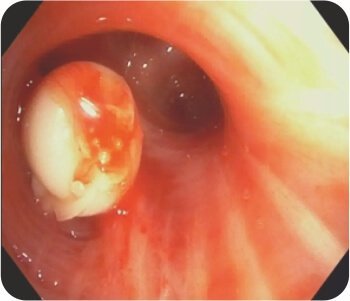

থোরাসিক এনজিওগ্রাম সহ CT বুকে হাইপারট্রফিড কোলাটারাল ধমনী সহ দ্বিপাক্ষিক গহ্বরের ক্ষত প্রকাশ করে যা প্রধানত ডান উপরের লোব গহ্বর সরবরাহ করে। FOB করা হয়েছে ডান উপরের লোব ব্রঙ্কাস থেকে সক্রিয় রক্তপাত দেখায়।

সক্রিয় হেমোপটিসিস